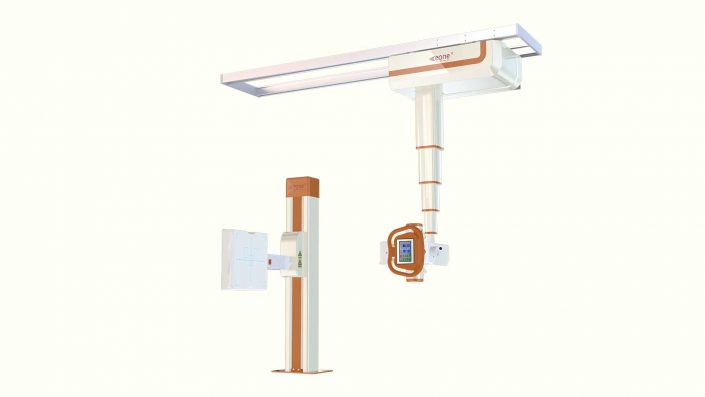

平板DR設備停機前與停機后有哪些注意事項?關于懸吊DR停機前注意事項:

DR影像簡介:直接數字平板X線成像系統,應用于:臨床醫學,影像部份能夠上下、左右移動,對全身骨骼、心血管、呼吸系統、五官、神經系統進行高質量拍片。

關于懸吊DR 開機前注意事項:開機前需要確認整機使用環境;開機前需要確認設備間環境溫度;長時間停機上電曝光不得使用大KV、mA;長時間停機上電前一定要確認三相輸入電壓;長時間停機上電前一定要確認電網的穩定性;肉眼檢查一下設備間是否有小動物鉆入的痕跡;平板要上電4個小時以后才能曝光。